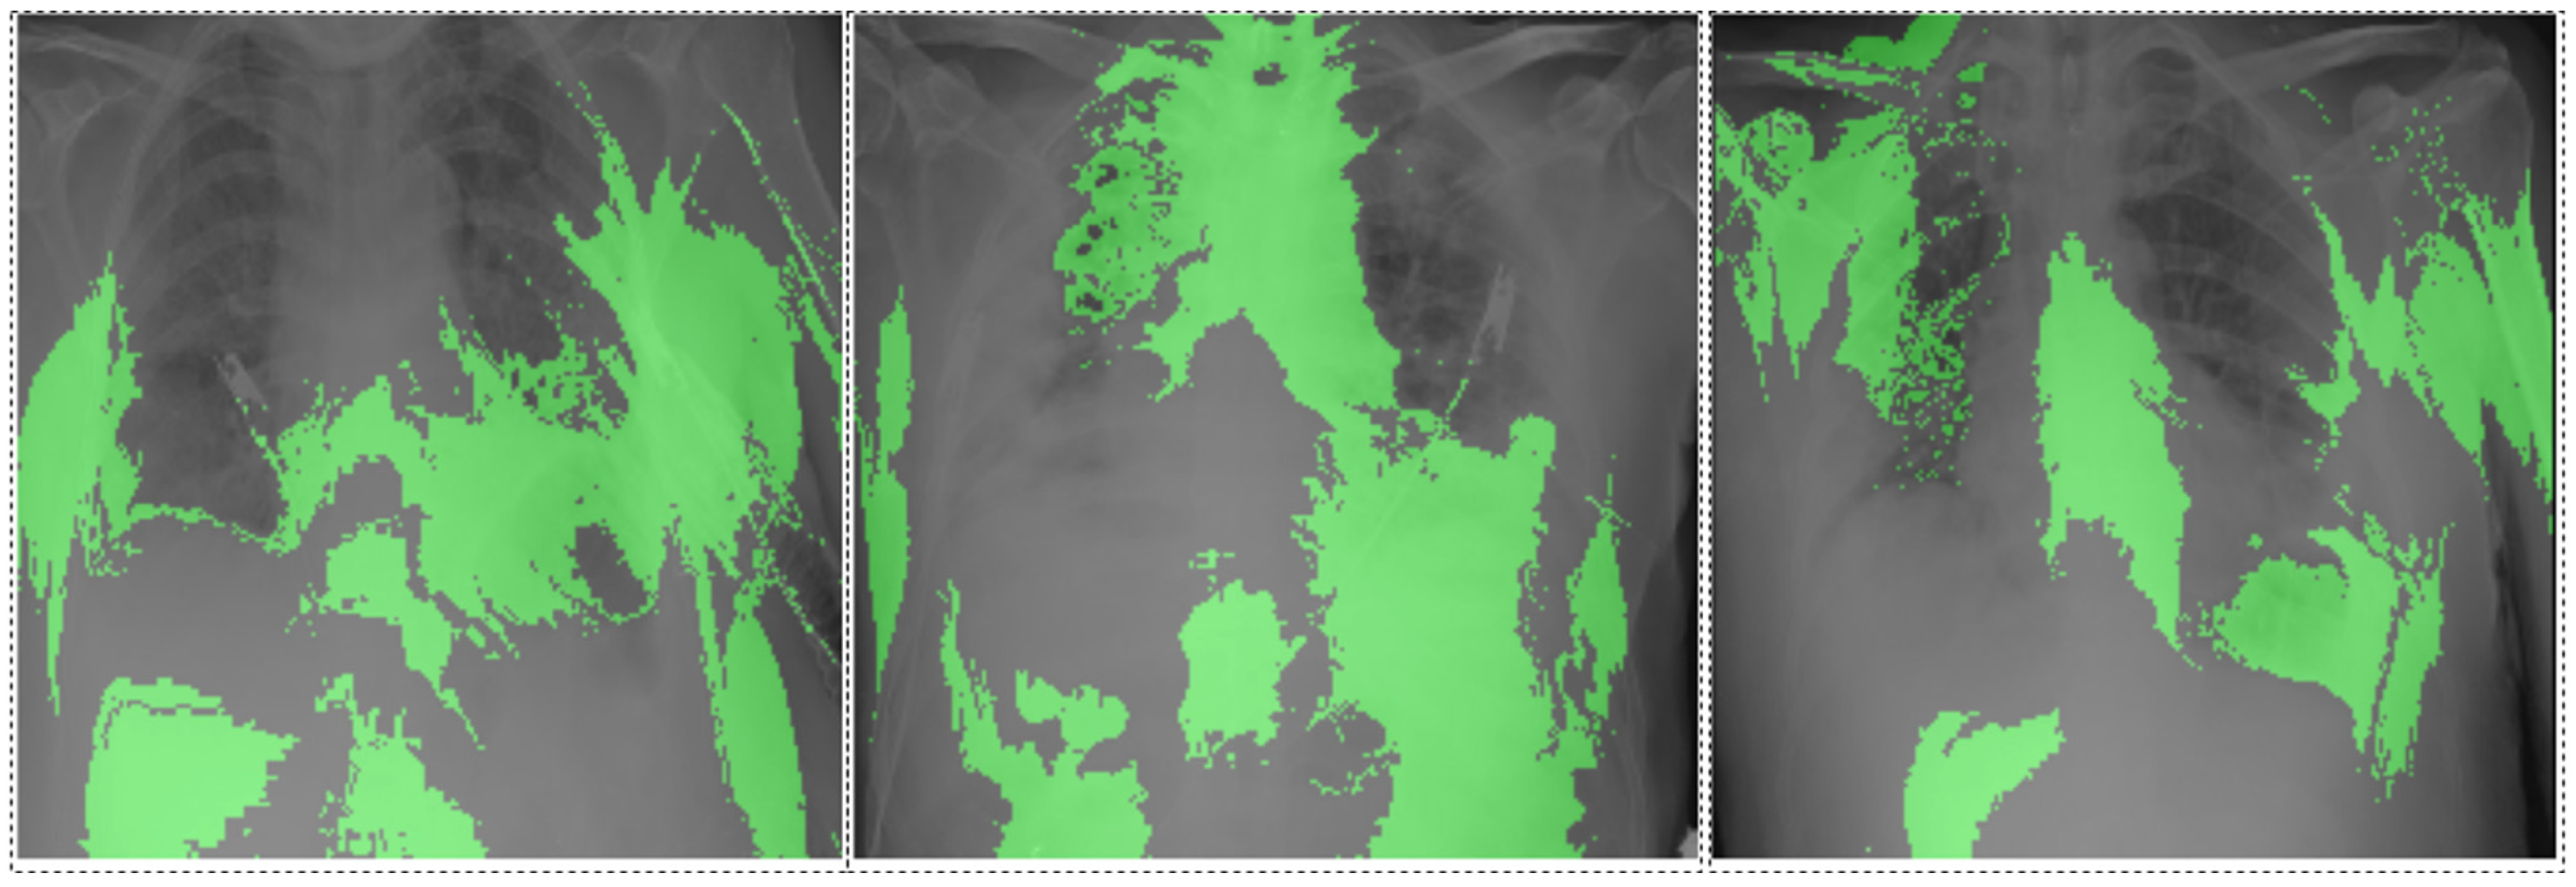

3.7. Interpretability Analysis